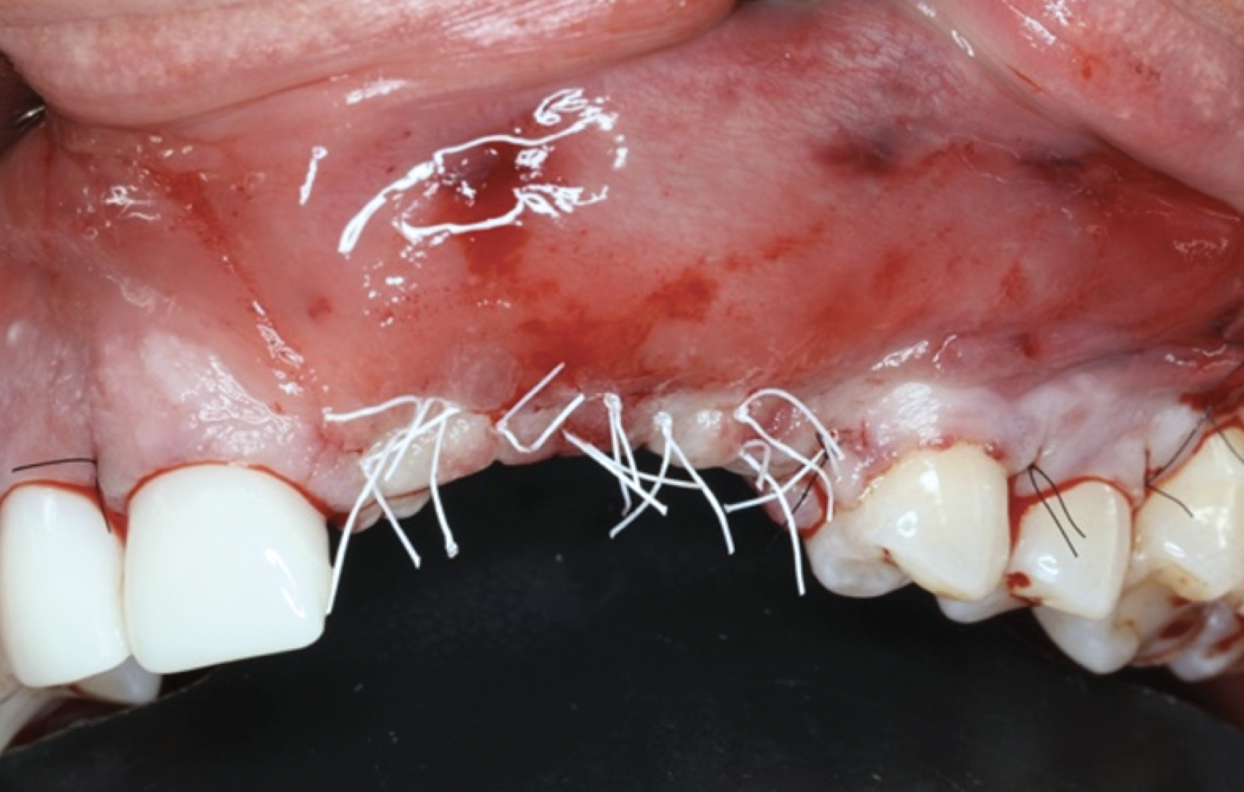

This approach was effective in increasing the horizontal and vertical soft-tissue thickness around the three implants. Nevertheless, a distortion of the MGJ was still present (Figure 13). Therefore, 3 months after the iCTG augmentation, it was decided to perform a second soft-tissue augmentation procedure with the goal of repositioning the MGJ in an adequate level on the buccal aspect, increasing the width of the keratinized mucosa at the implant sites. A modified apically positioned flap was performed (Figure 14). Two labial strip gingival grafts were harvested from the anterior mandible and maxilla and sutured onto the recipient bed with a 7-0 polyglycolic acid resorbable suture.5,17,18 The residual periostium was covered with a non-crosslinked xenogeneic collagen matrix (Figure 15).

Fig 13. Distortion of the mucogingival junction.

Figure 13

Fig 14. Modified apically positioned flap.

Figure 14